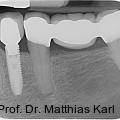

Parallel zur Entwicklung verkürzter Behandlungskonzepte haben sich auch die Außengeometrien zahnärztlicher Implantate hin zu aggressiveren Gewindeformen und konischen Grundkörpern entwickelt. Fotos: © Prof. Dr. Matthias Karl